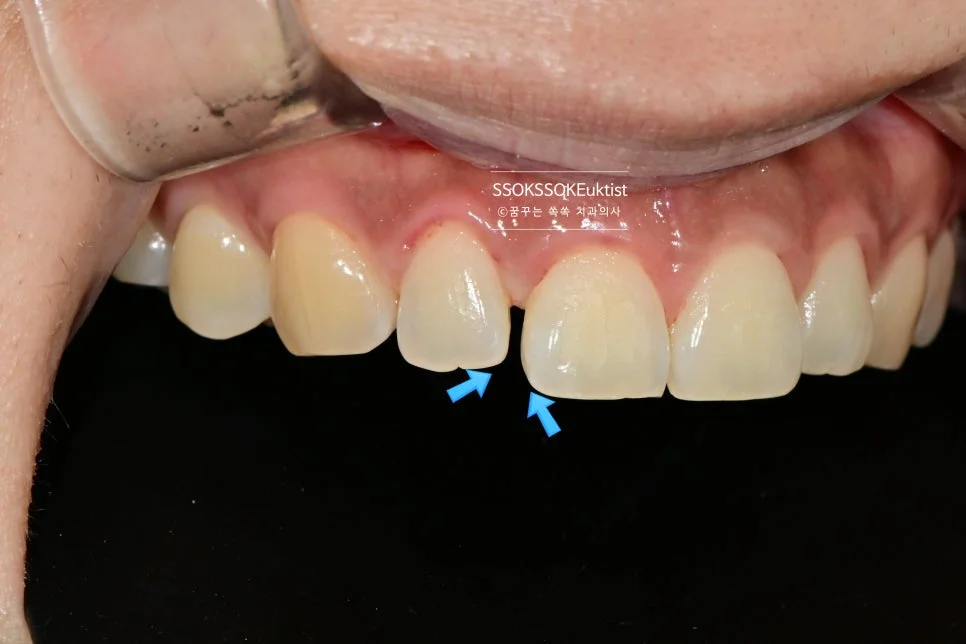

측면에서 바라본 사진입니다. 생각보다 틈이 커서 한 치아만 치료할 경우 한 개 치아만 너무 커 보이는 게 될 것 같아, 양쪽 치아 모두 레진으로 치료하는 것이 좋습니다.